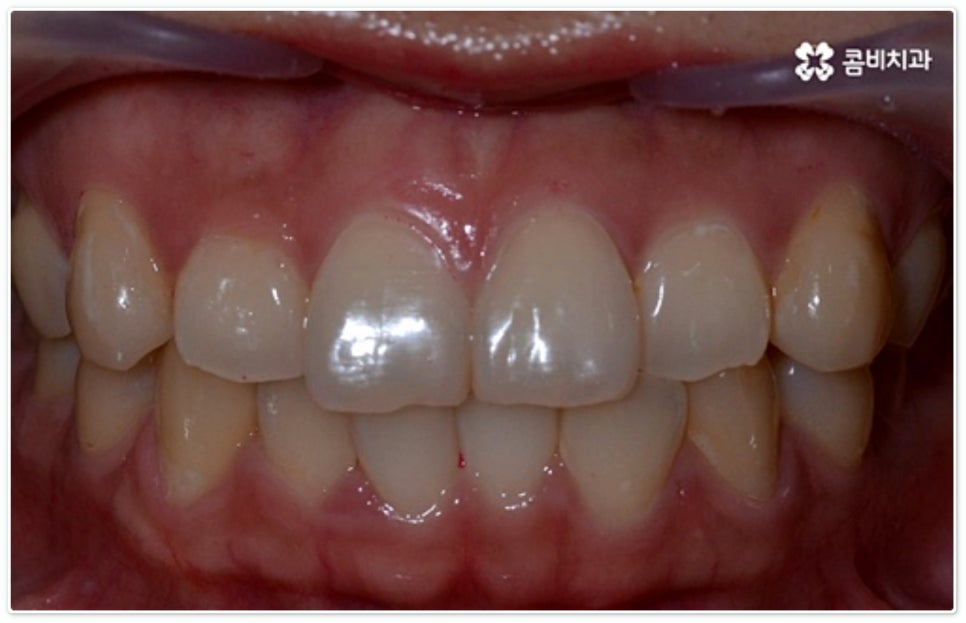

그렇지 않고 전후방 각도 조절 또는 단순 횡적인 움직임으로 치열 개선이 가능한 케이스는 부분 교정을 진행하는데, 사진에서 보시는 사례가 바로 그런 경우에 속하고 있습니다. 앞니 6개에만 브라켓을 부착하였는데 보시다시피 치아 색상과 유사한 세라믹 재질의 장치를 이용하여 심미성 또한 높여 주었음을 알 수 있어요.

토끼 앞니, 나비 앞니 중 이와 같이 어금니 교합은 정상이지만 앞니 또는 일부 치아가 돌출되거나 방향이 틀어진 경우 뿐 아니라 다른 치료 (보철 치료나 임플란트 시술) 를 위해 먼저 부분적으로 치아 이동이 필요한 경우, 교정 치료를 받은 적이 있으나 앞니 또는 주변 치아 배열이 다시 틀어진 경우 등에 있어서도 부분 교정이 이용될 수 있습니다. 그러므로 ‘치료가 오래 걸릴 것이다’, ‘장치가 보이는 게 많이 부담스럽다’, ‘재교정을 받는 것이 무섭다’ 등등 여러 걱정으로 교정 치료 시기를 미루시지 말고 필요한 경우 상담부터 차근차근 진행해 보시면 좋을 거예요.